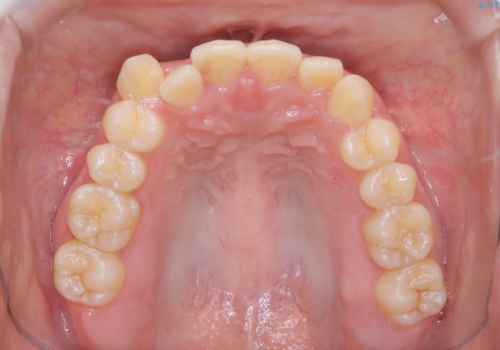

- 非抜歯、インビザライン治療希望の患者様です。

右の犬歯が八重歯になっており、通常であれば抜歯を選択する可能性が高くなりますが、

マイクロインプラントと呼ばれる骨に打ち込むネジを使用し、非抜歯での治療計画を立てました。

マイクロインプラントを使用することで非抜歯での治療が可能となりました。

マイクロインプラントを使用せずに無理に非抜歯治療を行った場合、

治療後に出っ歯になってしまうなどの問題が起きる可能性が高いです。